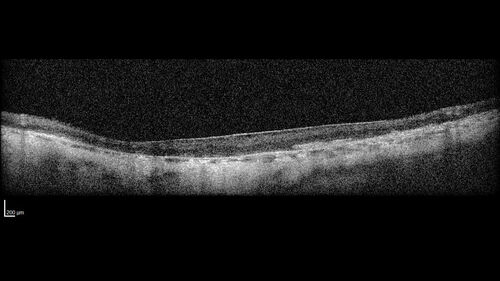

Optic Disc Melanocytoma - Atypical

45 year old female with normal vision and optic nerve lesion in the left eye. VA 20/16 OU. Extensive testing was normal including brain and orbit MRI. The lesion has been stable for 5 years.

AMD End stage both eyes - scar OD - GA OS